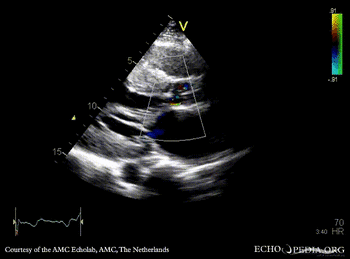

PLAX: subvalvular membrane in left ventricle outflow tract PLAX with Color Doppler: high velocity flow in left ventricle outflow tract